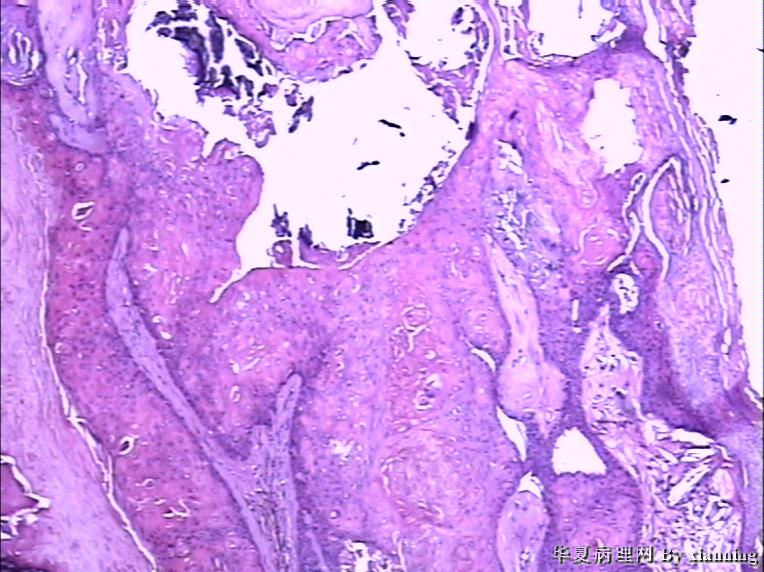

女 50岁 头皮下肿块

巨检:灰白色不规则结节0.9*0.7*0.4cm3,切面灰白色实性质地中等

名称:图4

描述:36580006